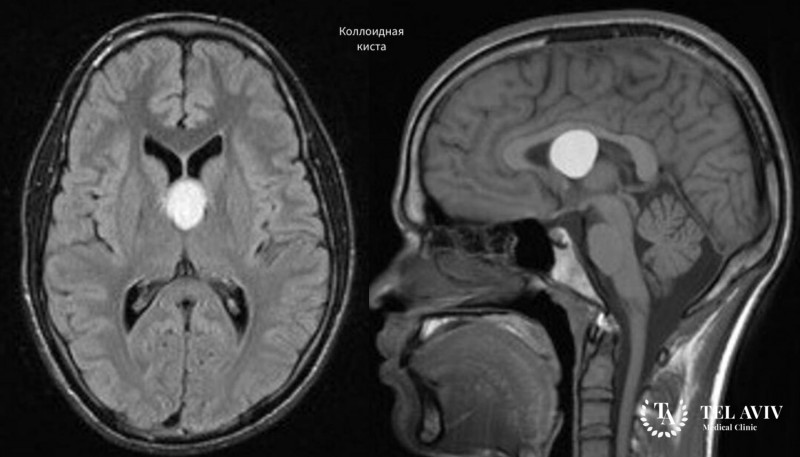

- Коллоидные новообразования в мозге вырастают до больших размеров, вызывают гидроцефалию.